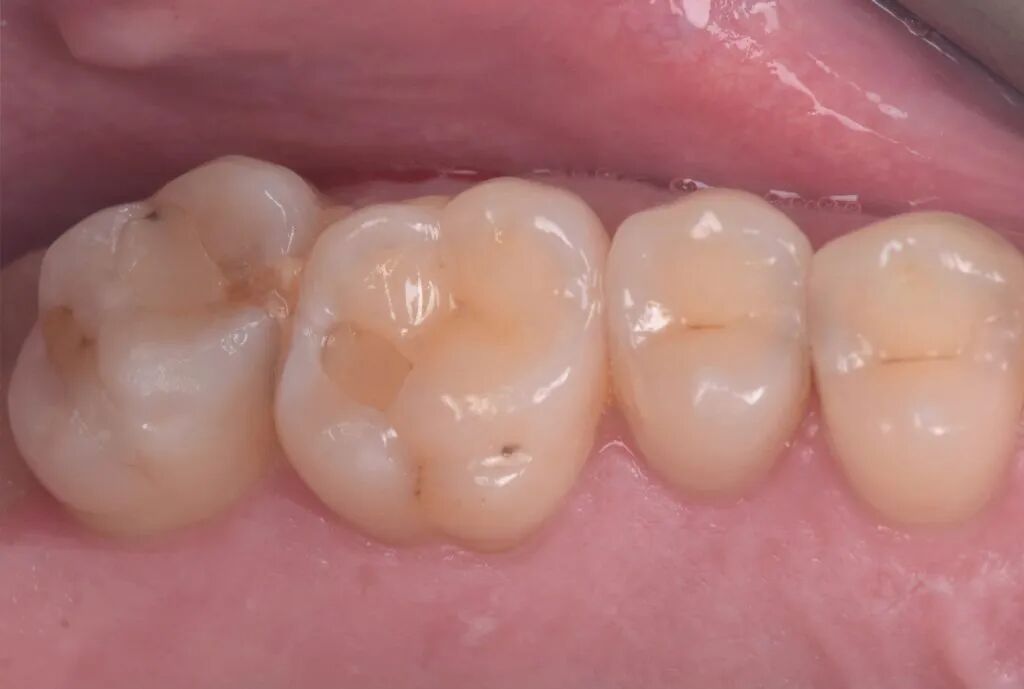

图15. 充填修复后,抛光,拆除橡皮障(此时牙齿仍处于脱水状态偏白),咬合纸检查咬合。

图16. 抛除咬合高点及印记。